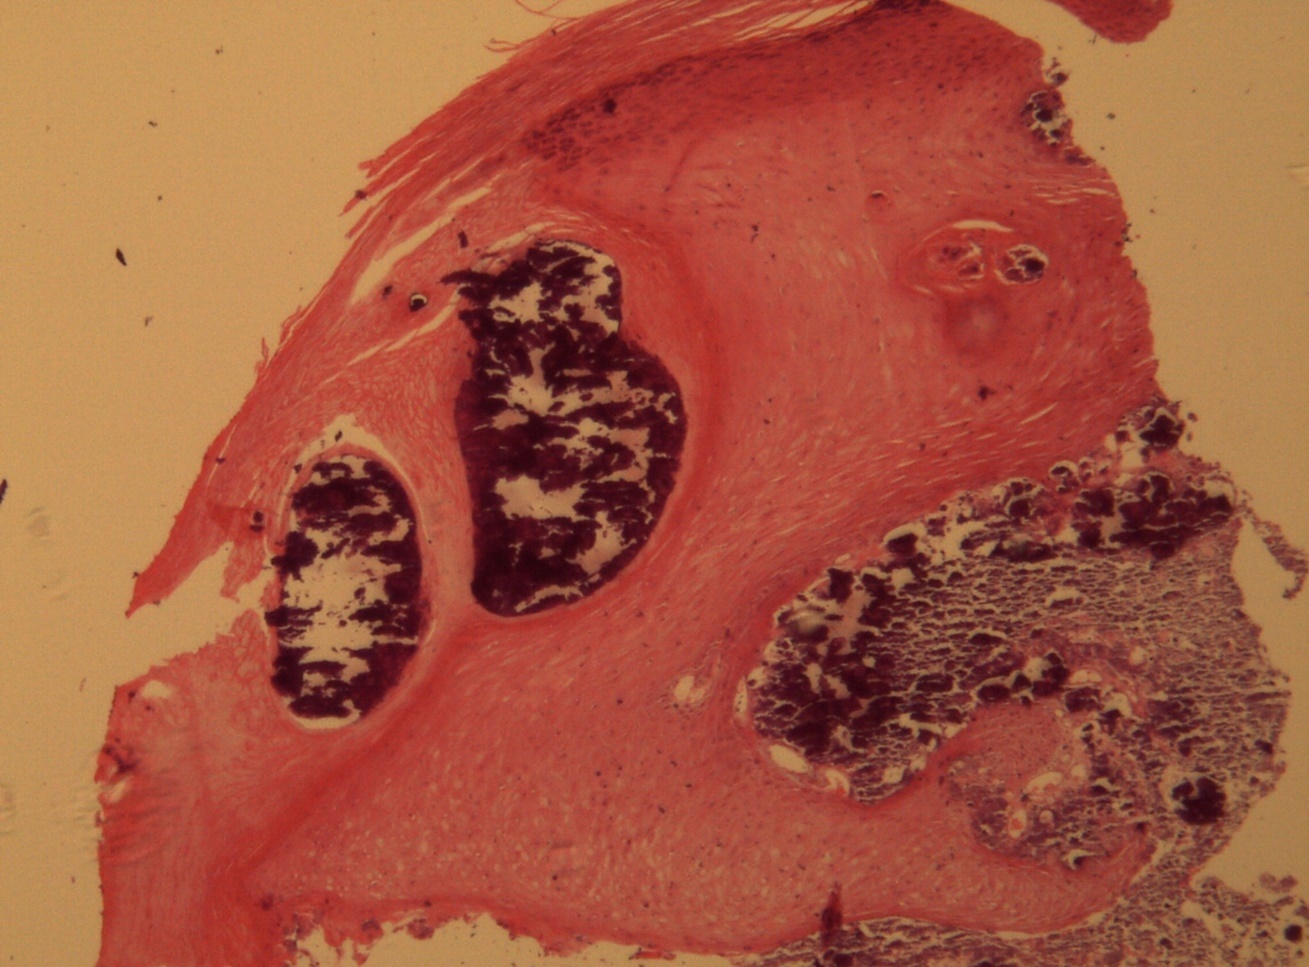

A 9-year-old male patient who was treated in the dermatology service for a progressively growing keratotic nummular dermal lesion on the right knee. With the clinical judgment of viral wart, the lesion was removed. In the Pathology Service, a nummular keratotic lesion of 0.5 cm in maximum dimensions was received, which crackled when cut. Figure 1, Figure 2, Figure 3, Figure 4, Figure 5

Figure 1.Hyperkeratosis, hypergranulosis, proliferation of dermal vessels, and surface and deep calcium deposits. HE. 100x.

Hyperkeratosis, hypergranulosis, proliferation of dermal vessels, and surface and deep calcium deposits. HE. 100x.